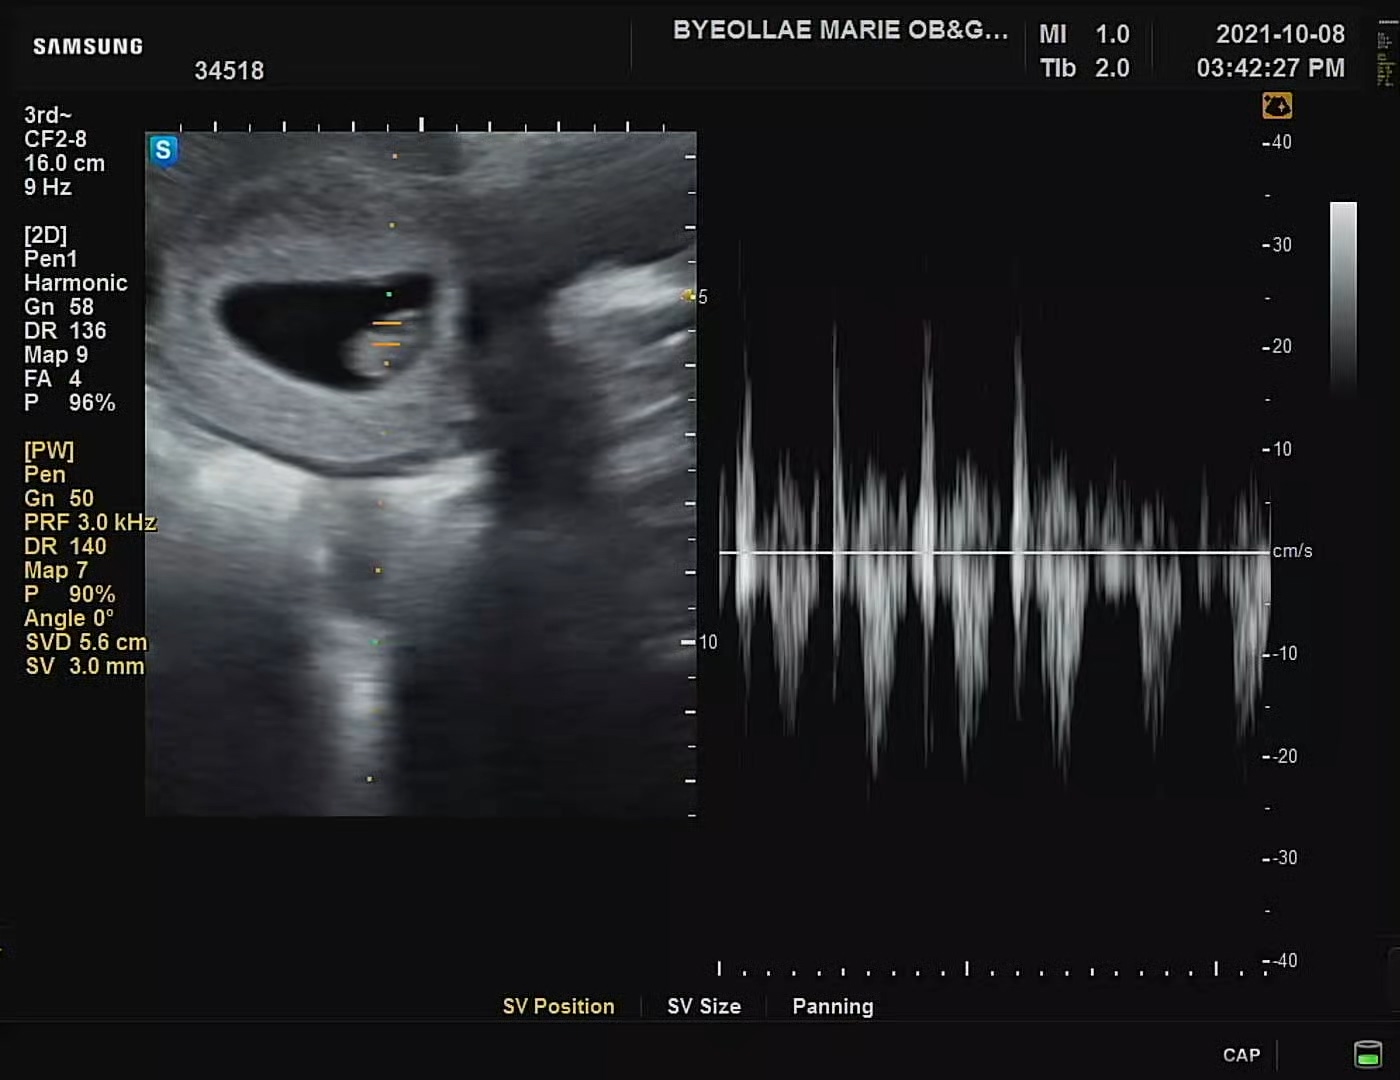

아직 1.4cm 젤리곰임에도 불구하고 씩씩하게 뛰는 심장소리. 생전 처음 들어보는 소리에 너무나도 신기하고 놀라웠다.

지금까지 방이 하나뿐이던 아기의 심장에 성인과 똑같은 4개의 방이 만들어지면서 활동을 시작한다. 어른 2배 정도의 분당 150회의 속도. 때문에 더욱더 씩씩하게 들렸던 우리 까꿍이의 심장소리♥